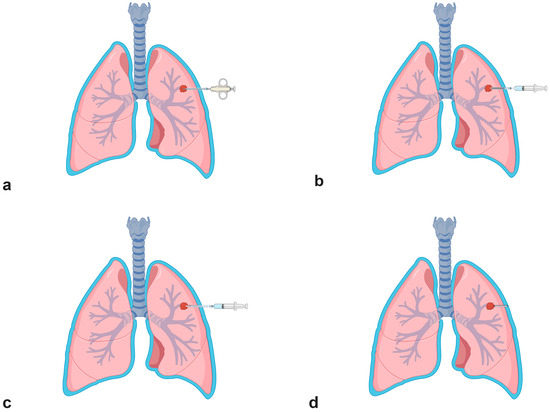

- Procedure technique